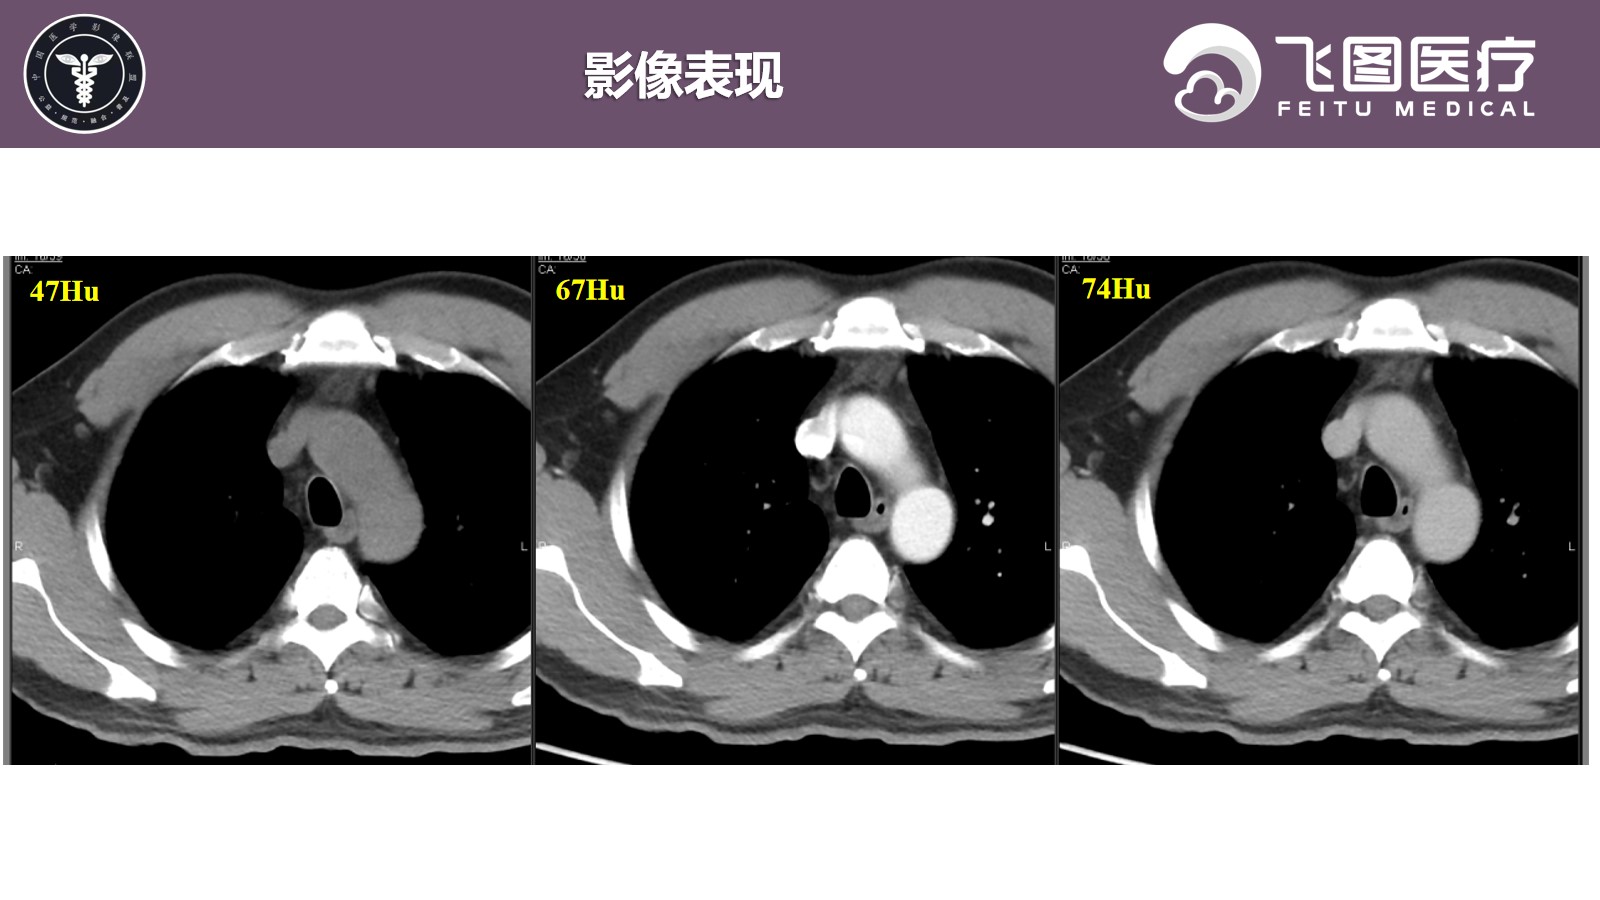

患者,男,50岁,因“检查发现右上纵隔肿物1月余。”入院。

现病史:患者于1月余前因“胆囊结石并胆囊炎”于我院治疗。查胸部X片提示右肺尖区斑片状密度增高影,倾向后纵隔来源占位性病变。患者平素无咳嗽、咳痰,无胸闷、气促,无呼吸困难等。

既往史:因“胆石症”行“腹腔镜下腹腔粘连松解+胆囊切除术”,术后病情较前好转,复查无异常,出院诊断: 1.胆囊结石伴有急性胆囊炎; 2.胆囊息肉; 3.黄疸; 4.肝功能检查的异常结果; 5.纵隔肿物; 6.肺结节; 7.脾大; 8.轻度贫血。